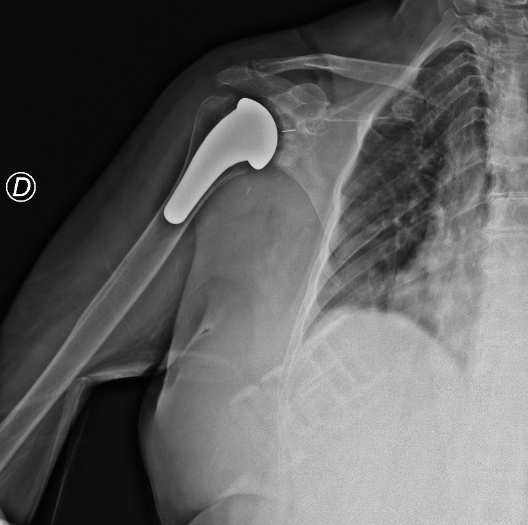

Rx | Inviateci le vostre immagini radiografiche

Inviateci le vostre immagini radiografiche

• Se sono in formato tradizionale, per potercele fornire è sufficiente fotografarle appoggiandole ad una superficie luminosa, come per esempio lo schermo di un computer purché sia aperto su di una pagina bianca. Dopodiché inviate le foto digitali alla mail info@claudioascani.it

• Se sono in formato digitale potete semplicemente allegarle alla nostra mail info@claudioascani.it

Valuteremo il vostro caso e vi risponderemo con la nostra diagnosi nel più breve tempo possibile.